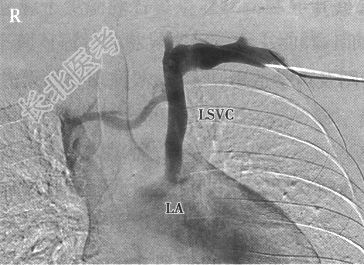

- 多项选择题3.患者上肢静脉造影结果见下图,根据上述结果, 可选择的手术方式包括( )

A、左上腔静脉在主动脉前由人工血管与右心房行端端吻合,近心端切断或缝扎

B、左上腔静脉经心包横窦由人工管道与右心房行端端吻合,近心端切断或缝扎

C、建立心内隧道将左上腔静脉经未闭卵圆孔引流入右心房

D、左上腔静脉结扎术

E、同期闭式封堵卵圆孔

F、采用封堵器介入封堵左上腔静脉